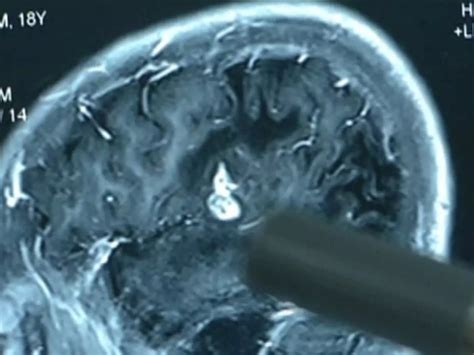

5-Inch Worm Removed From Chinese Man's Brain, It Was There For 17 Years

Living Worm Found Inside Australian Woman's Brain In A Medical First

Splainer | The scary case of a worm in Australia